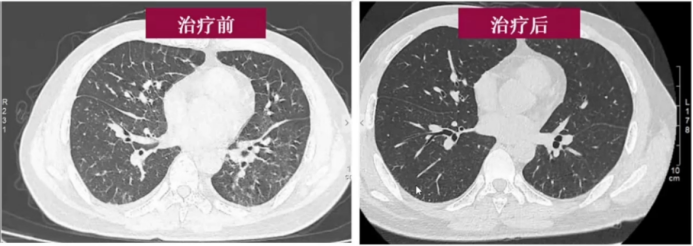

结合患者病史(服用呋喃唑酮)、影像学表现(小叶间隔增厚)及检查结果(无肾功能异常、心影不大),考虑为药物性过敏(呋喃唑酮所致)引发的肺水肿。

治疗方面,入院后停用呋喃唑酮,予甲强龙40 mg/d治疗3天,复查显示体温正常,两肺病灶基本吸收(图5),验证了诊断的合理性。

图片

5 患者治疗前后胸部CT对比